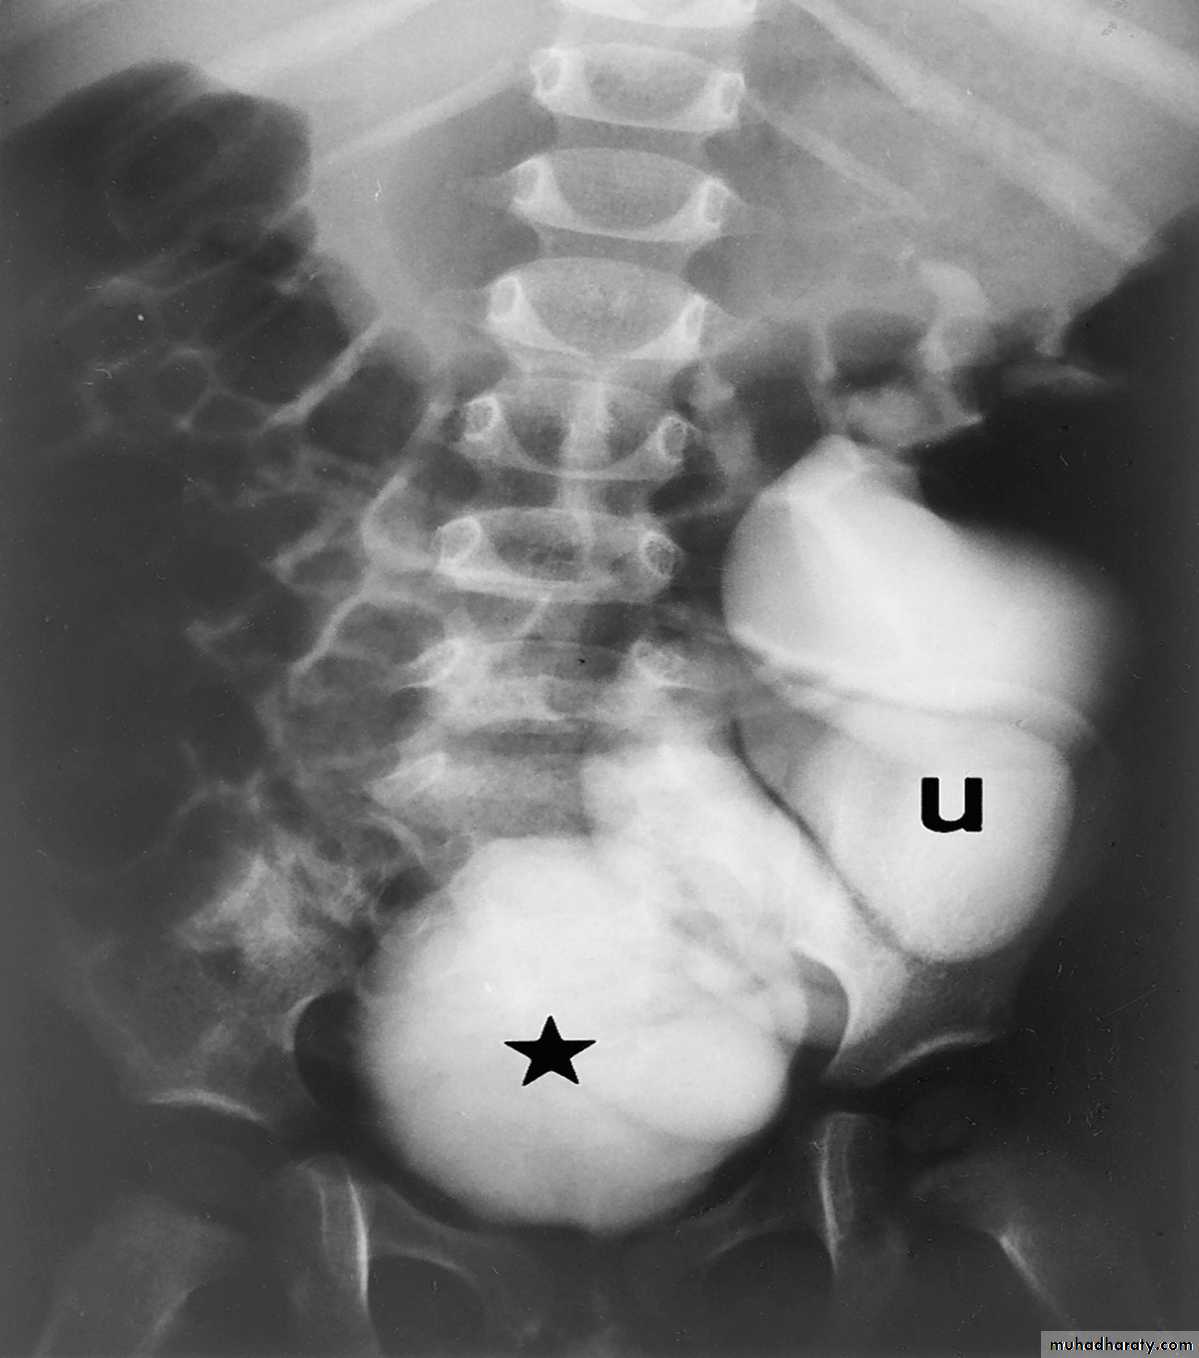

IVU

Large kidney .

Lobulated out-line.

Distortion of pelvi- calyceal system depend on cyst size, number and position.

In advanced cases there is elongation and stretching of minor and major calyces ( spider leg).

In advanced cases IVU shows non-functioning kidney .